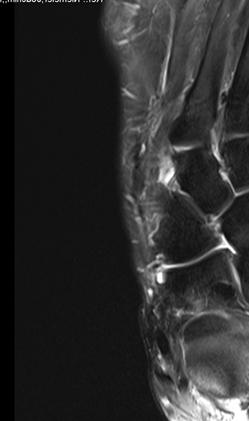

Bei einer Verlaufskontrolle im Juli 2017 ergab sich bei der Röntgenuntersuchung eine Fehllage einer Plattenschraube, die damit das TMT 2 überbrückte.

5.- 07/2017 Schraubenfehllage : Schraube erreicht Basis MT2 und überbrückt TMT 2

Im CT vom September 2017 ergab sich noch kein Durchbau der Arthrodesen, aber ein Bruch der das TMT 2 überbrückenden Schraube.

6.- 09/2017 Schraubenbruch